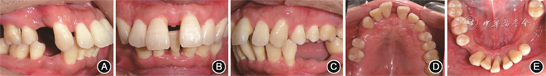

(1)牙周基础治疗:2017年6至11月,拔除预后无望患牙17、36、41、44和3颗第三磨牙18、28、48,完成龈上洁治、龈下刮治及根面平整术,使用复方氯己定含漱液(口泰,深圳南粤药业有限公司)含漱(20 ml/次,2次/d,10 d),并口服奥硝唑(固特,湖南九典制药股份有限公司)分散片(500 mg/次,2次/d,5 d)。复查显示口腔卫生良好,牙龈色粉红,质地坚韧(图4)。由于上前牙仍然存在PD>5 mm的位点,且根尖X线片显示11、21间牙槽骨呈垂直型吸收,建议行牙周再生性手术。

像;B:正面

像;C:左侧

像;D:上颌

面像;E:下颌

面像